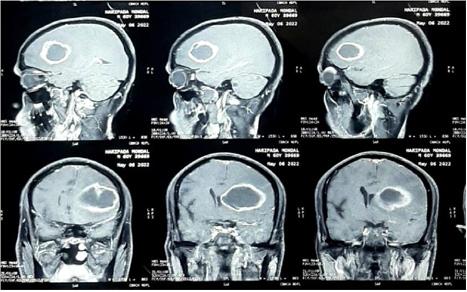

Materials and Methods : 90 Patients were selected during the study period as per the inclusion and exclusion criteria. Clinical scoring was done by NIHSS (National Institute of Health Scoring System). CT (Computed Tomography) scan of brain and MRI (Magnetic Resonance Imaging) Brain with DWI (Diffusion Weighted Image) extension was done. EEG findings on admission of morbidity was done by Modified Rankin Score on follow up after 1 month was noted. EEG findings after 1 month was noted on follow up. Assessment Clinical correlation was compared with EEG changes. All the data were collected and analysed by statistical software SPSS version 20.

ANALYSIS AND RESULTS

In our study most of the patients were in the age group of 61-70 years (45.6%), followed by the 51-60 years age group. Range of age was 51-85 years. Females were 44.4% and Males were 55.6% of the study-population. MRI of Brain with DWI extension revealed - 63.3%, 14.4%, 4.4% of the cases had MCA territory infarction, Multi-infarct state, ACA territory involvement respectively. On admission, 58.9%, 18.9%, 14.4%, 7.8% of the cases showed Normal EEG, Focal, Diffuse slowing and Multifocal slowing respectively. During follow up at 1 month, 91.8% of the cases showed Normal EEG, Focal and Diffuse slowing was noted in 4.1% cases each. The mean MRS after 1 month for abnormal and normal EEG on admission was 4.30 and 3.68 respectively, p value being 0.024 (significant). Among the abnormal EEG on admission the mean values of MRS were 3.29±0.59 and 5.77±0.44 in cases with focal slowing and diffuse slowing respectively, with p value of <0.001 (significant). The mean values of MRS were 3.36±0.8, 4.0±0, 5.0±0 in cases with normal EEG, focal slowing and diffuse slowing of EEG on follow up, with the p value of 0.006 (significant). In our study all Normal EEG on admission were focal lesions. Among abnormal EEG findings 64.86% and 35.14% were with focal lesions and Multi-infarct state respectively with p value being <0.001 (significant). During follow up all of the normal EEG was of patients with Focal lesions and abnormal EEG findings were equal among focal lesions and multi-infarct state with p value of <0.001 (significant). Our study shows 73.58% and rest of normal EEG on admission were with Subcortical lesions and Unifocal lesions respectively. Among the abnormal EEG 66.67%, 4.17% and rest were of unifocal, subcortical and multifocal lesions respectively, with p value <0.001 (significant). Our study showed 96.43% of cases with MCA territory infarct had normal EEG after 1 month in comparison to

68.42% on admission, which was statistically significant. Also 3.57% of cases with MCA infarct showed EEG with focal slowing after 1 month against 19.3% on admission, which was also considered significant. Significant improvement was also found in case of multifocal slowing of EEG in MCA territory infarct. 90.0% of PCA territory infarct showed normal EEG after 1 month against 54.55% on admission, with a significant p value. 10% of them had focal slowing after 1 month in comparison to 45.45% on admission, which was statistically significant. 91.67% of cortical lesions showed normal EEG after 1 month in comparison to 37.84% on admission with p value of <0.001 (significant). 8.33% of them showed focal slowing after 1 month in comparison to 43.24% on admission, which was statistically significant. Significant improvement change in multifocal slowing of EEG in them was also found. This study showed good clinical outcome in patients with ACA, MCA and PCA infarct. Whereas, Pontine infarct and those with Multi-infarct state showed very poor clinical outcome with high mortality. The p value of this correlation was found significant. The mean MRS after 1 month for ACA, MCA, PCA, Multi-infarct and pontine infarct respectively were 3±0, 3.44±0.91, 3.73±1.19, 5.77±0.44, 6±0. Multi-infarct state was associated with high mortality rate, whereas, cortical or subcortical lesion showed good clinical outcome according to MRS after 1 month which for cortical, subcortical and multi-infarct state respectively were 3.54±0.77, 3.7±1.34, 5.77±0.44. The p value of this study was also significant (Tables 1 & 2).